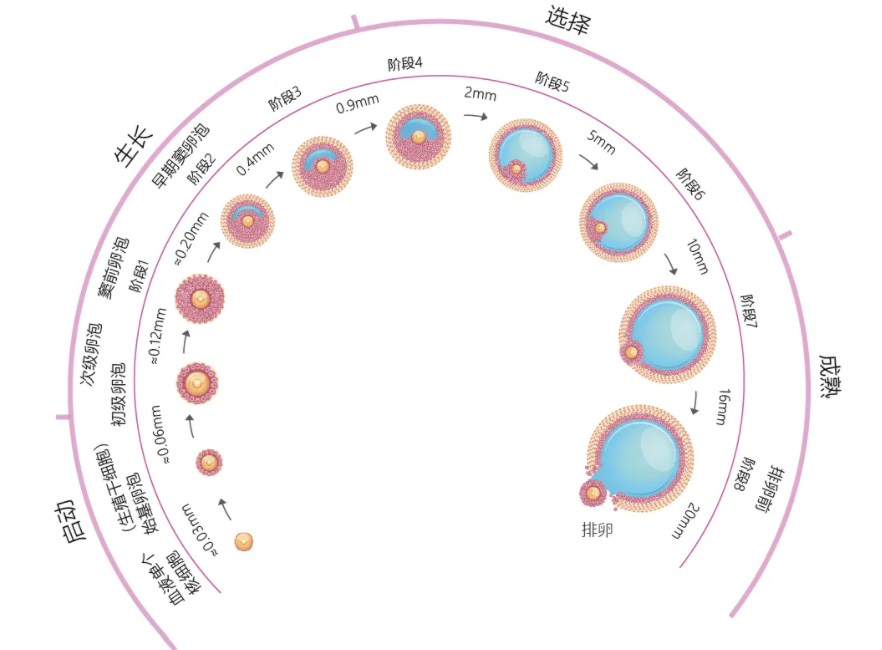

正常情况下,每个基础卵泡中都会有一个没有发育的卵细胞。女性每个月经初期,双侧卵巢上会有几个到几十个不等的基础卵泡产生。赴美做试管,专家会使用促排药物促使这些基础卵泡生长发育。但在超声监测下只能看到这些卵泡的数量,看不到里面的卵子。

卵泡只有发育成熟才能诱发排卵,此时排出的卵子才会成熟健康且功能健全。而卵泡成熟的特征是呈圆形或椭圆形、直径达18-25mm、卵泡内呈无回声区、清亮纯净、边界清晰。若女性因卵巢疾病,如多囊卵巢综合症、下丘脑-垂体-卵巢轴功能异常或是内分泌紊乱等,导致卵泡发育不良,就会造成取卵数量降低,与前期看到的基础卵泡数量不同。

取卵时机是决定获卵率的关键。如果时间把握不到位,会出现因卵泡发育不成熟而取不到卵子,或卵子过于成熟、老化流失的现象,从而降低获卵数量。所以用药第7天,专家会查看女性雌激素、孕酮和卵泡的数值,把握合适的取卵时机。当有1~2个卵泡发育直径≥18mm或2~3个≥17mm时,就开始注射破卵针,待36小时后进行取卵。